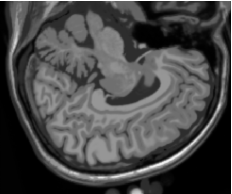

As figuras 2 (banda 0), 3 (banda 1) e 4 (banda 2) mostram a fatia 97 de um volume de imagens sagitais com 181 fatias e 0% de ruído, ponderadas em PD (densidade de próton), T1subscript𝑇1T_{1} e T2subscript𝑇2T_{2}, enquanto a figura 5 ilustra a composição colorida R0-G1-B2 da mesma fatia. Pode-se notar no topo do crânio, na parte inferior das imagens, a presença de artefatos, que podem ser resultantes de erros no simulador, mas que não são prejudiciais à análise, uma vez que, neste trabalho, não é dada ênfase à análise anatômica.

Figura 2: Imagem de RM da fatia 97 ponderada em PD

Refer to caption